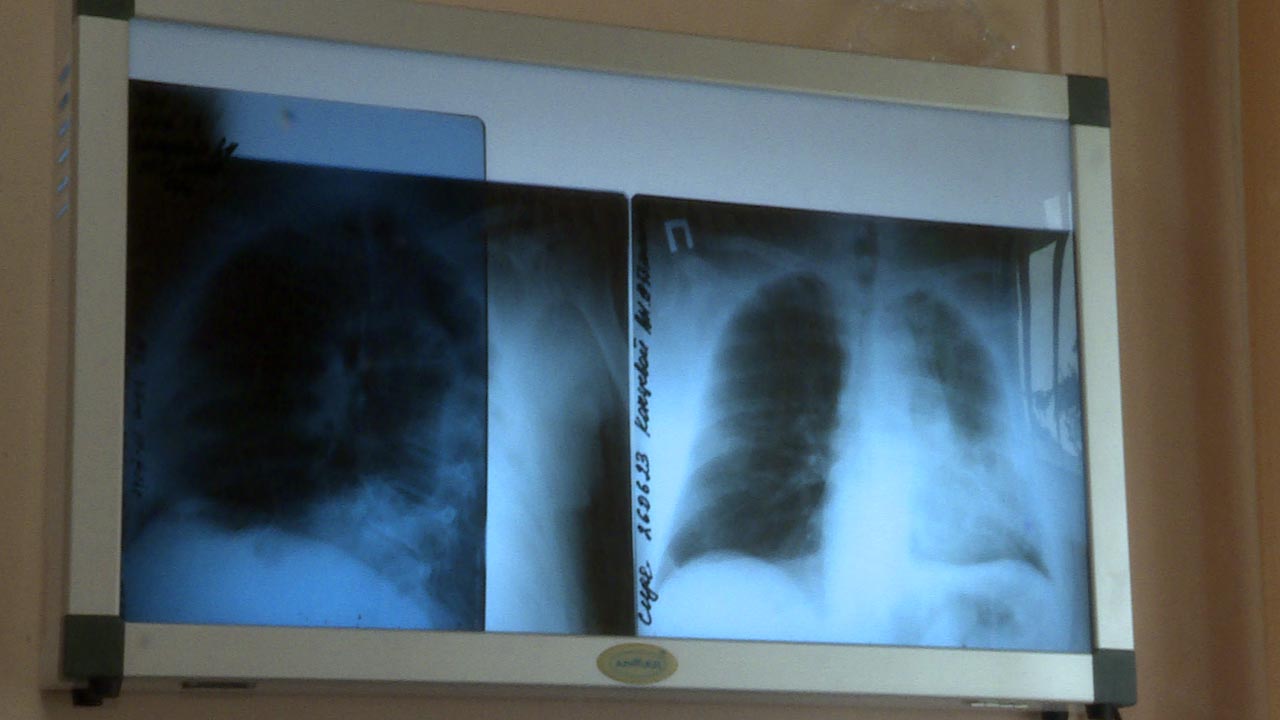

В региональном минздраве рассказали, что с 6 по 12 мая проходит Неделя сохранения здоровья легких в честь Всемирного дня по борьбе с астмой, отмечаемого 7 мая.

В связи с этим медики напомнили, что астма - это хроническое воспалительное заболевание дыхательных путей. Оно проявляется различными респираторными симптомами: свистящими хрипами, одышкой, заложенностью в груди, кашлем.

"Для профилактики и контроля астмы важно регулярно наблюдаться у врача, соблюдать рекомендации по лечению и избегать контакта с аллергенами", - подчеркнули в калужском министерстве здравоохранения.

В числе главных факторов, мешающих нормальной работе легких, специалисты называют курение, недостаточную физическую активность и избыточный вес.